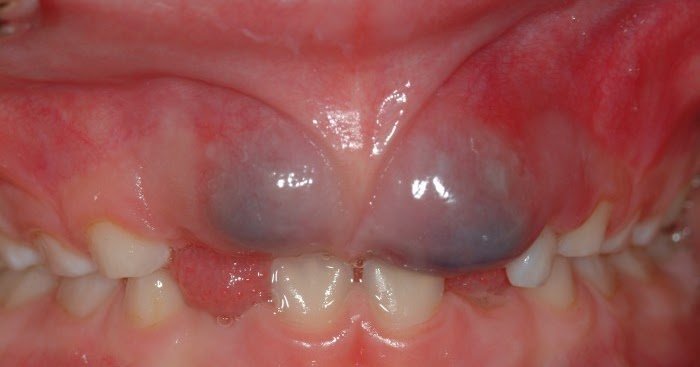

Флюс, або ж гострий періостит, — це запалення окістя, часто стає наслідком неякісного лікування зубів або . . . карієсу? Так, саме він! Карієс, цей замаскований ворог, який підкрадається тихо. Дитячі зуби ще слабкі, емаль ще не така міцна, тому карієс може бути дуже агресивним, і зупинити його складніше.

- Набрякання ясен. Це очевидний сигнал. Якщо дитина скаржиться на дискомфорт у роті, зверніть увагу на наявність припухлості.